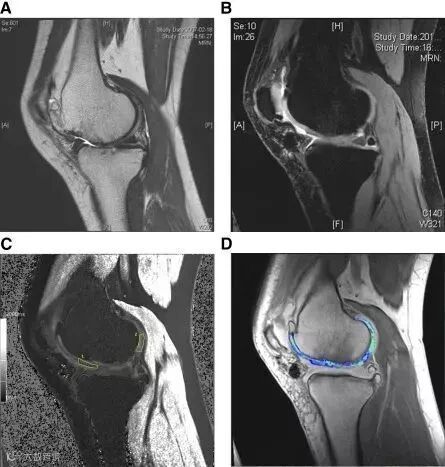

△ 在MRI中可见移植3年后的软骨再生

△ 软骨修复(I / II期试验)

左上:植入前; 左下:术后1年